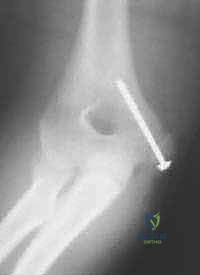

- التثبيت الداخلي (Internal Fixation):

- المسامير (Screws): غالباً ما يتم استخدام مسامير طبية مجوفة (Cannulated Screws) ومجهزة بخيوط جزئية لضغط القطعة المكسورة بقوة ضد العظم الأصلي.

- اختبار الثبات والحركة: قبل إغلاق الجرح، يقوم الدكتور هطيف بتحريك المرفق في جميع الاتجاهات للتأكد من ثبات التثبيت، وعدم وجود أي احتكاك، وتأكيد استعادة نطاق الحركة الكامل.